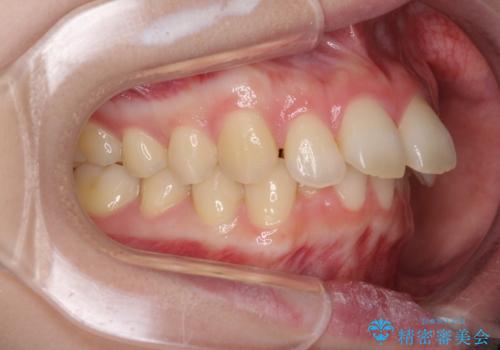

- 口元の突出感を気にして来院された患者様です。

左右ともに上顎奥歯が外を向き、下顎奥歯が内側に倒れているシザーズバイトであったため、補助装置により改善することとしました。

上下の咬み合わせは、下顎に対して上顎が相対的に前方にあったため、奥歯のシザーズバイト改善後に上顎左右第一小臼歯2本を抜歯し、上顎前突を改善していくこととしました。

左側の咬み合わせと上下正中の位置をコントロールするために時間がかかりましたが、事前に思い描いた通りの歯列に整い、患者様には大変満足していただきました。